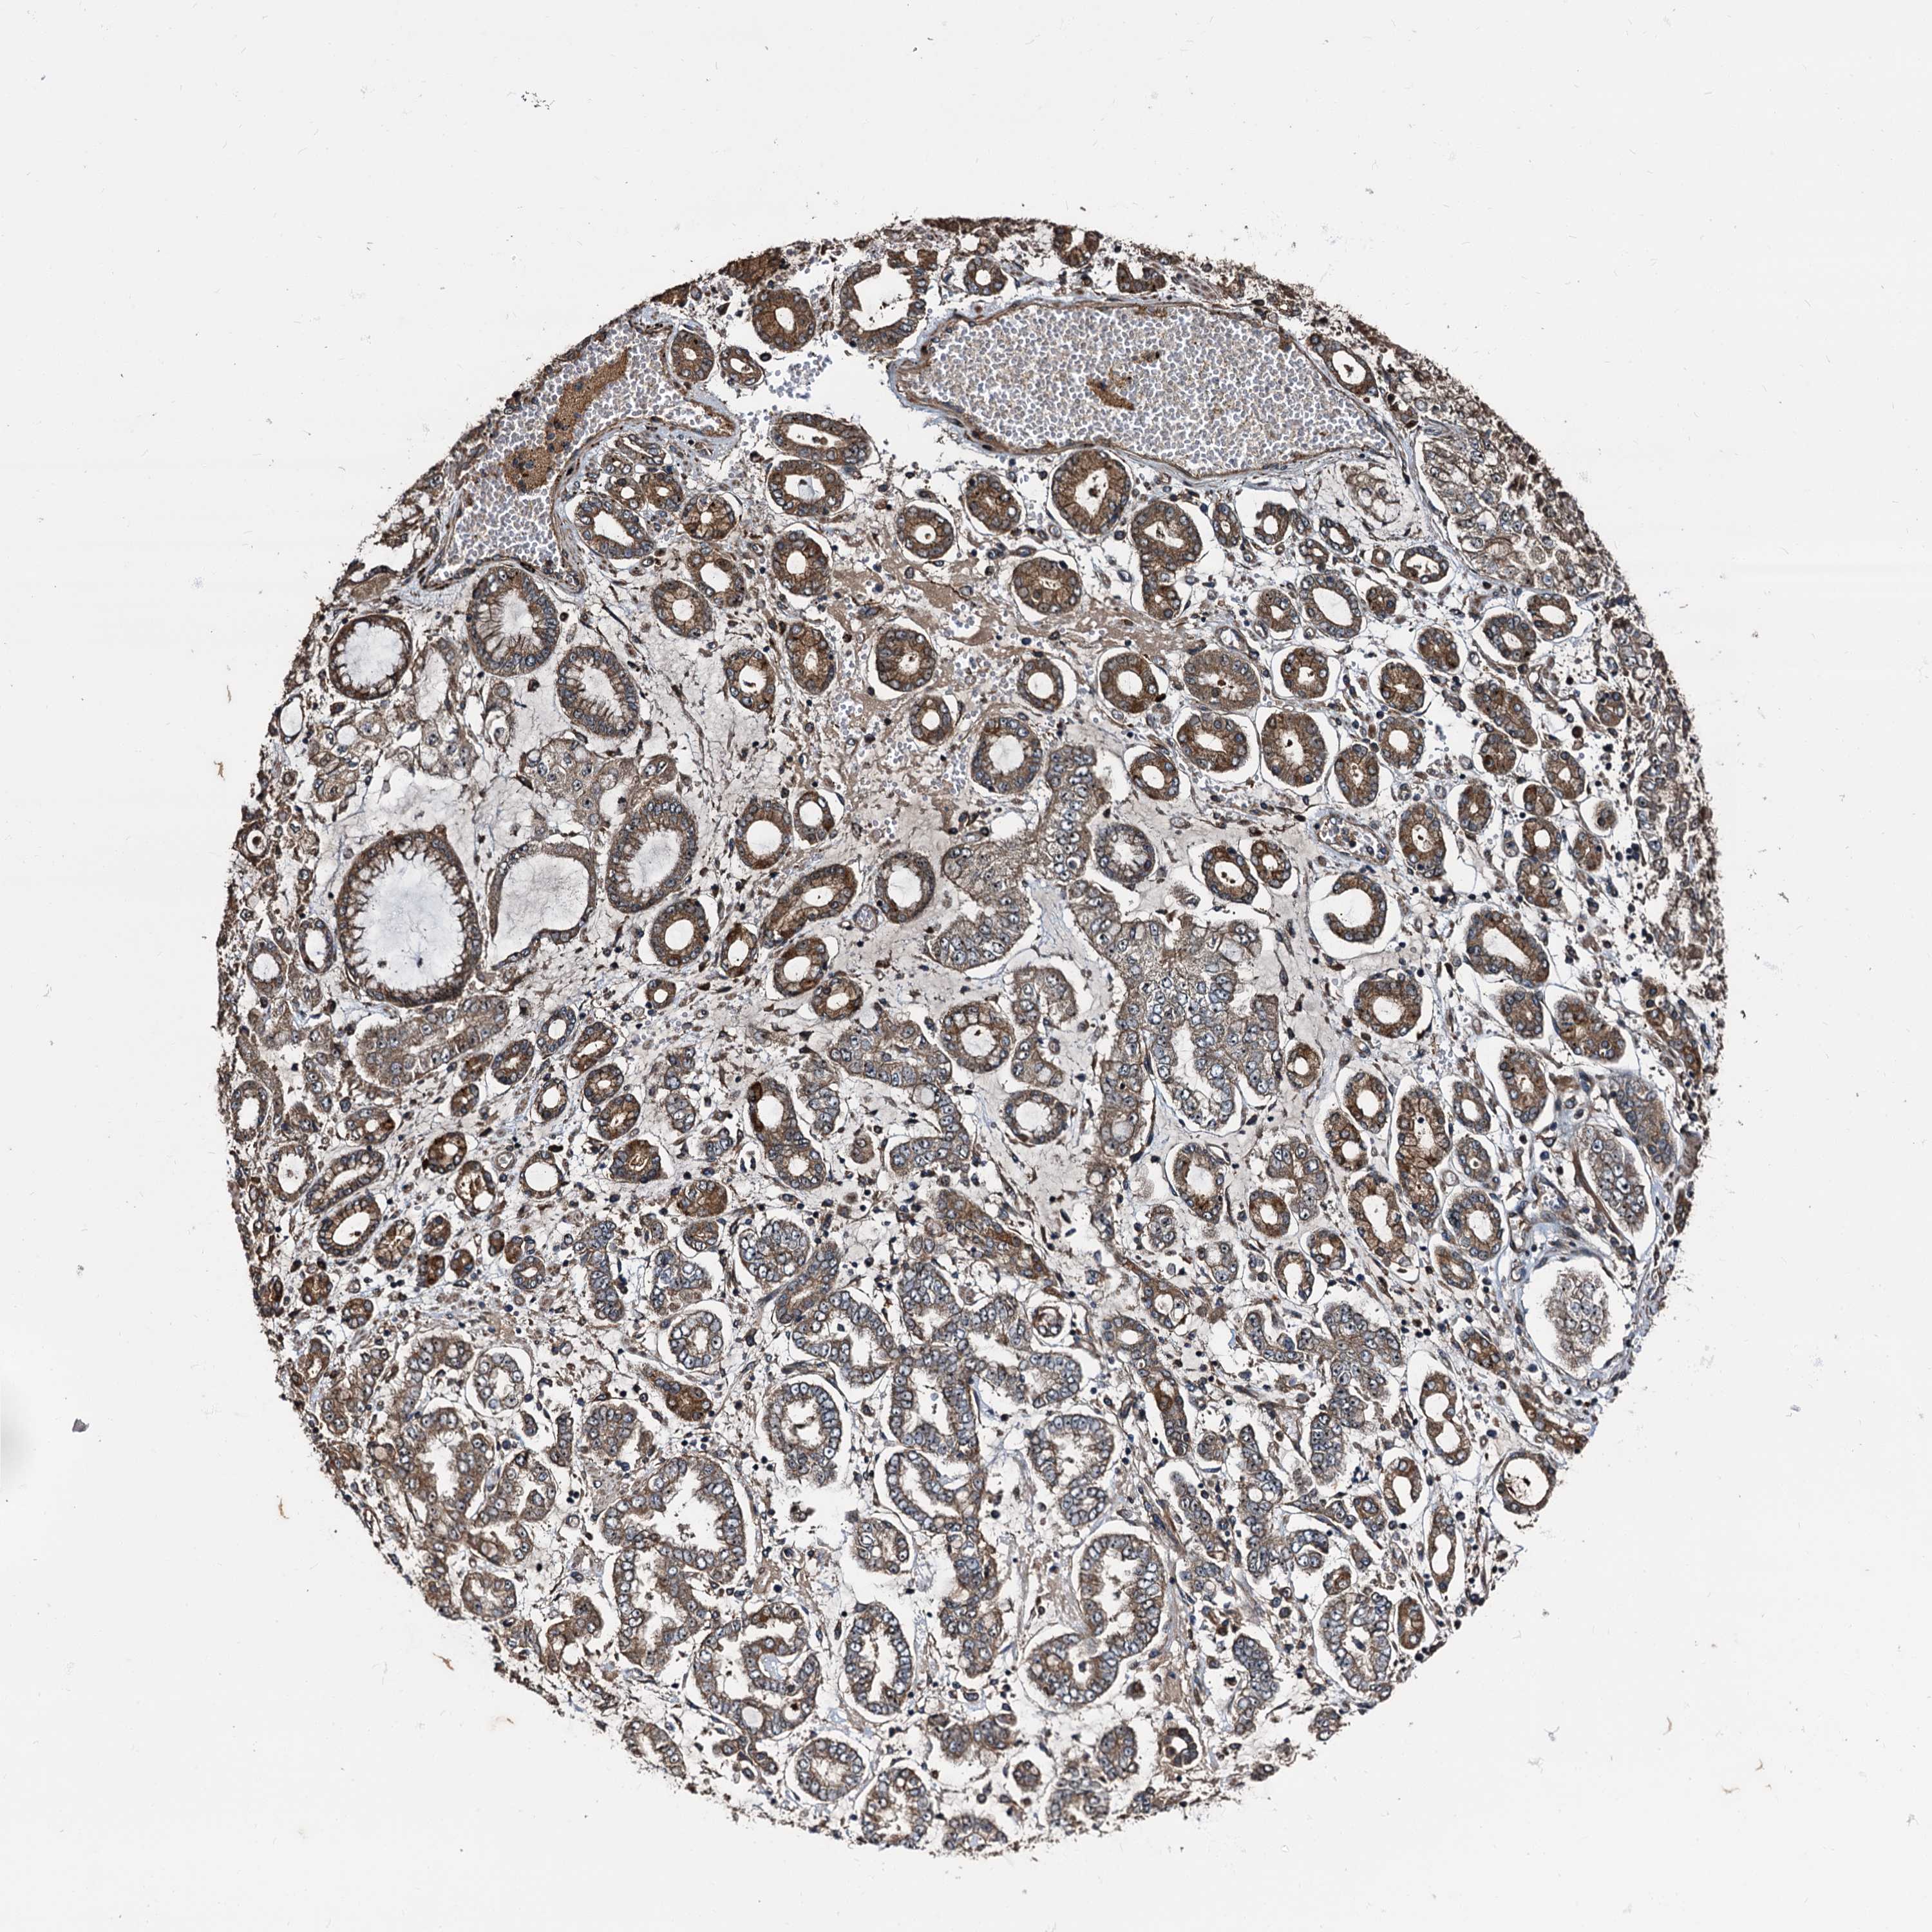

STOMACH CANCER - Protein expressioni

A mouse-over function shows sample information and annotation data. Click on an image to view it in a full screen mode. Samples can be filtered based on level of antibody staining by selecting one or several of the following categories: high, medium, low and not detected. The assay and annotation is described here.

Note that samples used for immunohistochemistry by the Human Protein Atlas do not correspond to samples in the TCGA dataset.

Antibody stainingi

Antibody staining in the annotated cell types in the current human tissue is reported as not detected, low, medium, or high, based on conventional immunohistochemistry profiling in selected tissues. This score is based on the combination of the staining intensity and fraction of stained cells.

Each image is clickable and will lead to virtual microscopy that enables deeper exploration of all samples and also displays staining intensity scores, fraction scores and subcellular localization as well as patient and tissue information for each sample.

Antibody HPA039259

Antibody HPA039260

Staining

High

Medium

Low

Not detected

Intensity

Strong

Moderate

Weak

Negative

Quantity

>75%

75%-25%

<25%

None

Location

Nuclear

Cytoplasmic/membranous

Cytoplasmic/membranous,nuclear

Adenocarcinoma, NOS